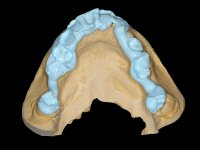

Com um pouco de prática e destreza, a anatomia de um único dente anterior pode ser reproduzida com relativa facilidade desde que os modelos nos forneçam informação detalhada dos dentes adjacentes. Em contraste a determinação e reprodução da cor/shade dentária é um assunto complexo e difícil, em que pequenos desvios podem ter impacto grande no sucesso do trabalho. Existem duas formas válidas para os dentistas comunicarem com o laboratório a informação relacionada com a cor/shade :1) Ou o dentista envia essa informação por meio de fotografia dentária digital, 2) Ou o paciente desloca-se ao laboratório dentário para que o técnico possa elaborar um esquema de estratificação. É importante ressalvar que um bom protocolo de estratificação, é só um primeiro passo na criação de uma restauração estética e não garante a sua “perfeita” implementação.

Neste caso a paciente foi vista no laboratório, o que tornou possível estabelecer o correcto nível de saturação da cor e brilho. Quando a construção da cerâmica estava optimamente ajustada em termos de cor/shade, os componentes da translucidez puderam ser finalmente acrescentados. Nesta fase foi também completada a anatomia e a textura superficial de acordo com a informação dada pelos detalhes reproduzidos no modelo. A caracterização com tonalidades e essências no ciclo final de cozedura é fundamental, permitindo um ajuste fino da caracterização.

A confecção de um coto de óxido de zircónio com uma coroa de cerâmica vítrea prensada de dissilicato de lítio mimetizou perfeitamente os dentes vizinhos.